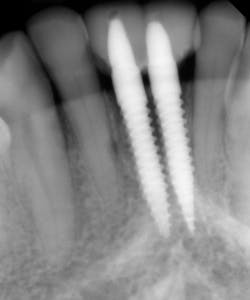

This patient presented with discomfort and mobile teeth Nos. 24 and 25. Extractions were performed, and the area was allowed to heal for six months. Mini-implants were placed in site Nos. 24 and 25 and immediately loaded with temporary crowns. The final splinted restoration was cemented two weeks later.

Figure 8: Initial implant placement DIO 3.0 x 16 mm implants

Figure 9: Implants restored two weeks after placement